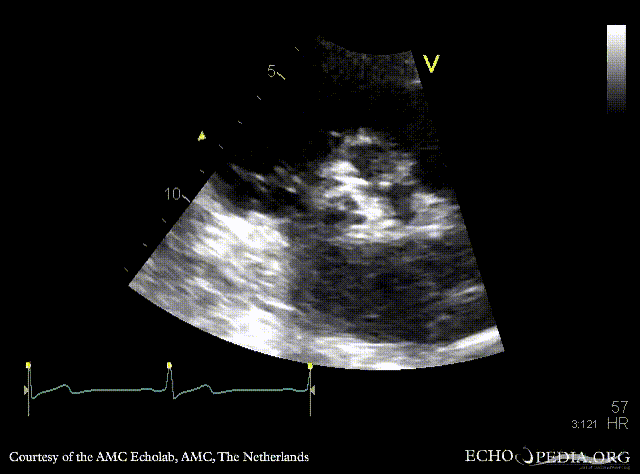

E00860.gif E00861.gif

PLAX: stenotic aortic valve, left ventricle hypertrophy PLAX with Color Doppler: mild aortic regurgitation